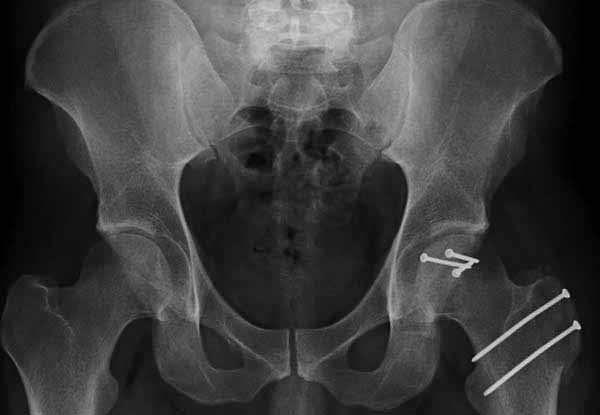

Представлены несколько вариантов фиксации: первый случай перелом головки с задним краем, операция из заднего доступа Кохер, а второй случай изолированный перелом головки - из трохантерного доступа.

Вложение не в текстовом формате было извлечено…

Имя     : 2-7 Fem head  fx-disl post reduction.jpg 0.jpg

Тип     : image/jpg

Размер  : 29867 байтов

Описание: отсутствует

Url     : http://weborto.net:8080/pipermail/ortho/attachments/20111231/d311d17a/attachment-0013.jpg